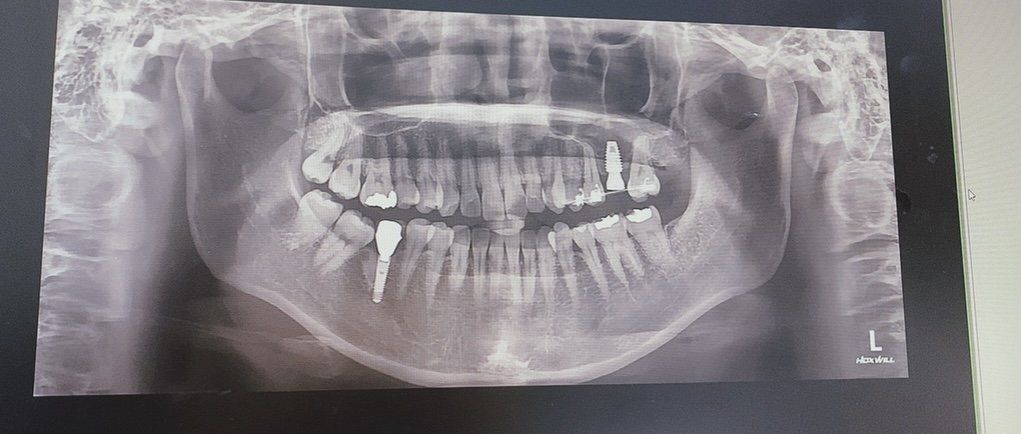

임플란트는 기존치아와 달리 뼈와 osseointegration으로 결합되어 있는 구조입니다. 즉 만약 임플란트가 움직인다면 상부 구조물인 머리 부분일 가능성이 가장 큽니다. 보통 움직이는 치아는 방사선 사진 상으로 관찰이 됩니다. 즉 임플란트와 그 옆에 치아를 촬영했을 때 방사선 사진으로 동요도가 있을지 어느정도 예상이 가능하기 때문에 관련 의료기관 의료진을 신뢰하지 않는다면 방사선 사진을 다른 의료기관에 문의해보시는 것도 도움이 됩니다.

-> 제 방사선 사진 저번에도 올려드렸었는데 상부 좌측 임플란트입니다. 저번에 말씀해주셨을때 치아에 이상 없음, 임플란트 방사선 투과성이 보이나 각도에 떠라 다를수있다고 해주셨는데 이 사진으로 흔들림을 볼 수있나요?

사진으로 보았을때 임플란트 끝 나사가 처음보다 내려와있는건가요? 그리고 머리 지점이 크라운과 맞닿는 부분인가요?

이 사진만으로는 확실하게 뼈가 녹았다는점을 말씀드릴 순 없습니다.

때문에, 사진만으로는 임플란트가 흔들릴 것이라 라는점을 알 수 는 없습니다.

물론, 뼈가 많이 녹은게 확실하다 라고 확신할 수 있을 정도로 사진으로 명확히 보일 때 도있습니다.

하지만, 올려주신 사진의 경우는 이에 해당되지 않습니다.

임상적으로 구강내를 검사해야 확실히 알 수 있습니다.